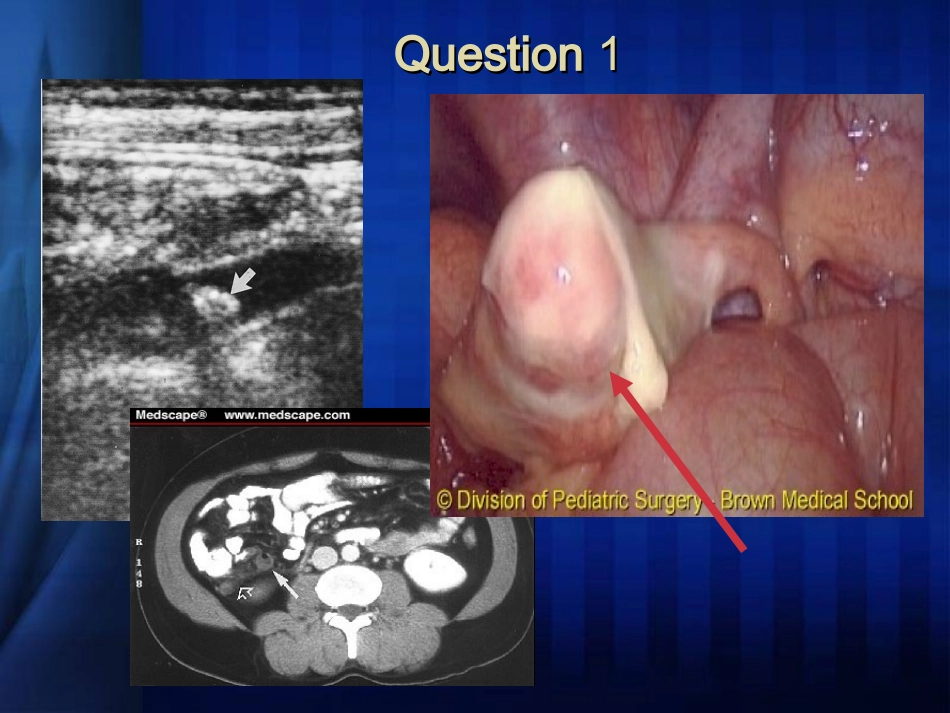

急腹症临床诊治思路急腹症临床诊治思路官店卫生院外科QuestionQuestion11Meckel’sDiverticulitisMeckel’sDiverticulitisWhat?Question2Question3螺旋CT尿路造影(CTU)QuestionQuestion44螺旋螺旋CTCT三维重建动脉造影三维重建动脉造影腹主动脉瘤Question5Question5Question6糖尿病酮症酸中毒尿毒症肝硬化腹水出血热肠系膜淋巴结炎肺炎冠心病心绞痛铅中毒腹型癫痫……思考与困惑??思考与困惑??医生最头痛的症状学最常见的主诉最易产生纠纷起病急,病因繁杂,病情多变,涉及学科广首诊的医生多是低年资医生,误诊、漏诊时有发生。急腹症的诊断——双刃剑??学好急腹症是当好一名大夫的基本功,更是行医安全的保障。惨痛的教训!!!惨痛的教训!!!急性腹痛+右侧阴囊包块诊断为右侧腹股沟嵌顿疝,手术中发现为乙状结肠自发性穿孔,右侧阴囊包块实为鞘膜积液。第一次手术切口第二次手术切口右侧阴囊肿块病例病例急性腹痛入院:中年男性,外地人,右上腹痛,无畏寒、发热,无皮肤巩膜黄染,刚开始生命体征稳定,逐渐出现血压下降等休克表现前一班处理:诊断考虑急性胆囊炎,未做彩超等辅助检查,给予抗感染、补液等治疗下一班医生的思考——感染性休克?失血性休克?处理——急诊彩超、诊断性腹腔穿刺最终诊断——肝癌结节破裂出血TwoPrimaryImportantQuestionsTwoPrimaryImportantQuestionsDiagnosisDifferentialDiagnosis临床诊断过程临床诊断过程搜集资料(病史、体检和辅助检查临床思维(综合、分析、推理)初步诊断修正诊断进行“去粗取精,去伪存真,由表及里”的思索病史——诊断钥匙病史——诊断钥匙系统真实重点突出——以腹痛为中心在病情尚不明朗,许多化验检查还没做,特别是遇到翻滚哭闹、不能主诉病情或配合检查的病人时,如何在尽可能短的时间内,对接诊的急性腹痛患者“理出个头绪”,或初步诊断,或为进一步检查提供个思路,是我们面临的首要问题。完整的病史是正确诊断的一半急性腹痛的问诊程序及技巧急性腹痛的问诊程序及技巧腹痛是个主诉症状,其很多内容,要靠病人自己或其家属叙述,可以说问诊是接诊急性腹痛患者过程中主要的诊查方式。要想在最短的时间内问出我们想要的、真实的东西,必须要有一个合理的问诊方法。什么样的问诊方法才算合理呢?问诊程序化问诊程序化也就是说问哪些内容、先问哪些、后问哪些,必须提前设计好,不能东一榔头,西一棒槌,把病人问烦了,我们什么也得不到。这里所说的“提前”是指平时我们就应该有一套设计好的腹痛问诊程序。其实这种“程序化问诊”的理念适用于所有临床学科。问话不仅要精练,还要通俗易懂,不能让病人存在理解障碍。问时间?问时间?下面有一种问法:病人:大夫,我肚子疼。大夫:多长时间了?这种问法合适吗?回答这个问题之前,先让我们来看一个例子:一个病人,前天上午腹痛发作,今天上午来看病,如果你问他多长时间了,他会说:三天。其实只有48小时!因为很多情况下病人说的是“虚岁”,而我们要的是“周岁”。很显然,“多长时间了?”的问法不合适。问时间?问时间?正确地问法应该是:肚子疼从什么时候开始的?如果这样问我们可能得到三种答案:1.能说出准确的发病时间。这类病人对腹痛发生的那一刻记忆犹新。甚至有的病人能说出几点几分。这种情况见于突然发病而且开始即为剧烈疼痛的病人。多由穿孔、破裂、梗阻等引起。2.说出大概时间。只能回忆起发病的大概时间。对发病的那一刻记忆不深。这种情况多见于开始疼痛较轻的病人。以后疼痛可以逐渐加重。多见于炎症性疾病。3.说不出发病的时间。这类病人一时记不起大概的发病时间了。往往需要大夫帮助他回忆。譬如说,如果他说晚上发病,我们会继续问他发病时吃没吃晚饭、睡没睡觉等帮助他尽可能的回忆起发病的大概时间。炎症疾病居多。问时间?问时间?至此,我们已经问出了一个发病的时间,那我们是不是就可以确认这个时间了呢?不见得!譬如说,一个病人说他腹痛时间大概在昨天下午4点左右。如果我们继续问,昨天下午四点以前痛不痛?有的会说:其实早晨起来就有点...